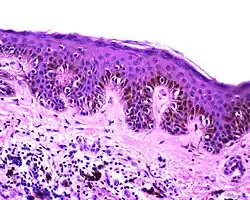

| Junctional nevus | Along the junction of the epidermis and the underlying dermis.[15] | May be colored and slightly raised.[16] |

ICD10: D22 ICDO: M8740/0 |